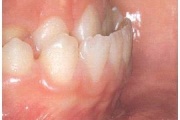

Ravijärgne seis. Jäävhammas on täielikult lõikunud.